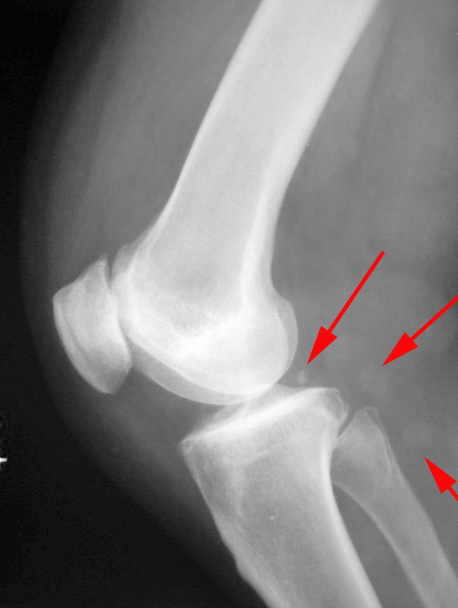

女.50.膝关节疼痛伴伸直困难.请会诊

退变,骨质增生,关节腔游离体,后方二个箭头似为滑膜钙化。

最上边是腓肠小豆骨,下边二个可能是滑膜钙化吧,

退变。正常子骨。膝关节内侧后方软组织结节影,考虑大隐静脉呈瘤样曲张。

退行性骨关节病;肯定不是游离体,正位与股骨外侧髁重叠,侧位在膝关节后方,为腓肠小骨(腓肠肌外侧头肌腱内常见的一枚子骨)。

右膝关节呈退行性改变,关节囊后方多个游离体,符合滑膜骨软骨瘤病。髌韧带增厚,边缘模糊,髌下脂肪垫密度增高,符合滑膜炎。

退变本身就包括关节腔内游离体。下面箭头考虑滑膜钙化

退变,游离体,滑膜结节。